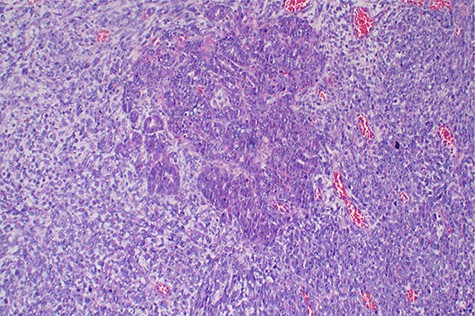

Explorative laparotomy was done, intra-operatively, and a complex cystic left ovarian mass was found with extensive omental and uterine carcinomatosis seedlings. The liver and spleen were normal. Omentectomy, total abdominal hysterectomy and bilateral salpingo-oophorectomy was done and the samples (Fig. 3) were taken for histopathology. The histopathology results revealed the presence of malignant mixed Müllerian tumor of the ovaries with metastasis to the omentum (Figs 4, 5). The rest of uterus was essentially unremarkable. The tumor cells were strongly positive for p53 immunohistochemistry (on both epithelial and stromal components) (Fig. 6). Furthermore, the epithelial component of the tumor was positive for epithelial membrane antigen immunohistochemistry, whereas stromal element was positive for vimentin.

Histopathology of the tumor showing malignant epithelial and sarcomatous elements, hematoxylin and eosin, ×40 magnifications.

Histopathology of the tumor with malignant epithelial and sarcomatous elements, hematoxylin and eosin, ×100 magnifications.

Malignant mixed Müllerian tumor of the ovary is a rare tumor that accounts for ~1% of all ovarian cancers [1, 2]. These tumors are typically large, ranging from 10–20 cm in diameter; our patient’s tumor was 15.6 × 7.1 × 6.1 cm (Fig. 3). The presence of an intimate admixture of malignant epithelial and stromal elements (Figs 4, 5) is the morphological characteristic feature of this tumor. The epithelial element is most commonly a high-grade serous or endometrioid carcinoma, but can be of any of the surface epithelial cell types of ovarian tumors. The stromal component usually contains sheets of hyperchromatic rounded to spindled cells with marked nuclear atypia and a high mitotic index (Fig. 5). Immunohistochemical stains for epithelial markers are often positive in the sarcomatous component, as it has been observed in the index case (Fig. 6), and their behavior and patterns of spread are similar to high-grade serous carcinomas [3–5].